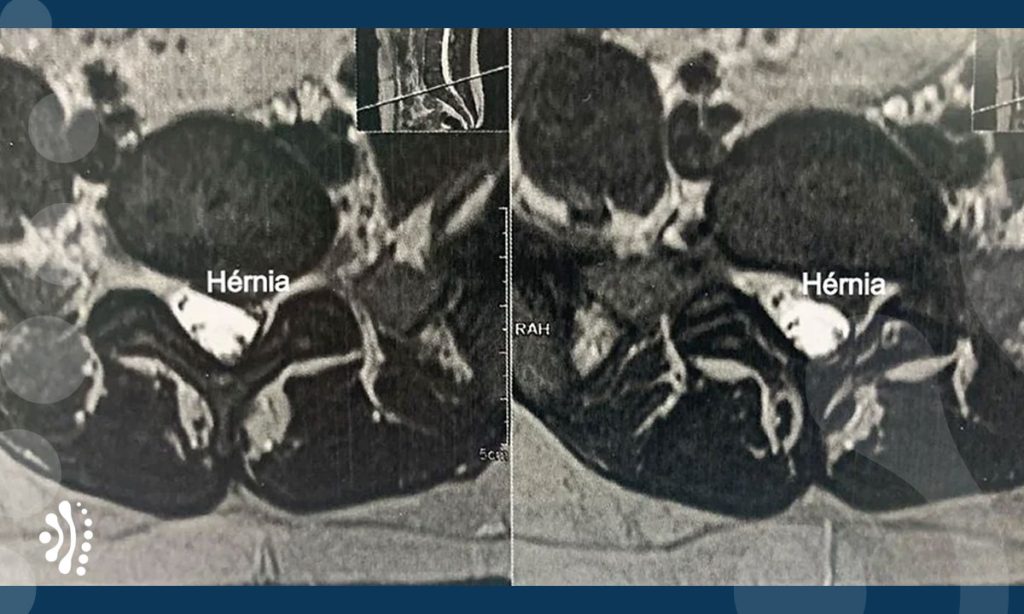

Hérnia de Disco Lombar

A Hérnia de Disco Lombar é uma condição na qual ocorre uma lesão que se situam entre as vértebras da região lombar.